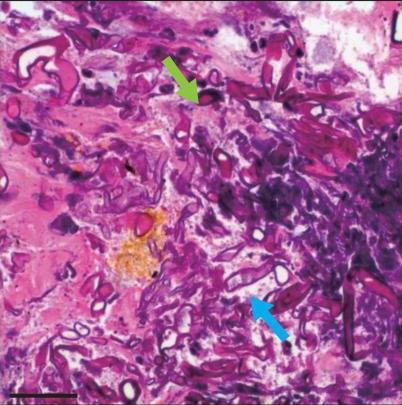

• 侵袭性肺真菌病的支气管镜表现及介入治疗效果

2025, 31(9):81-90. DOI: 10.12235/E20250317

摘要 (112) HTML (56) PDF 6.06 M (77) 评论 (0) 收藏

摘要:目的 探讨侵袭性肺真菌病(IPFD)的支气管镜表现,并评估介入治疗的安全性和疗效。方法 回顾性分析2018年5月12日-2025年5月12日于该院行支气管镜检查的35例IPFD患者的临床资料,观察IPFD的支气管镜表现及介入治疗效果。结果 共收集35例患者临床资料。其中,男22例,女13例,患者年龄(53±14)岁。基础疾病包括:血液系统恶性肿瘤10例,长期应用糖皮质激素者5例,2型糖尿病者4例,肺部恶性肿瘤2例,器官移植1例。胸部CT显示:肺部病变累及单肺叶者19例,累及多肺叶者16例。支气管镜下表现主要为:黏膜充血水肿29例(82.9%)、坏死物堵塞管腔22例(62.9%)、大量黏稠脓性分泌物17例(48.6%)、支气管部分狭窄或闭塞16例(45.7%)、黏膜坏死9例(25.7%)、黏膜出血5例(14.3%)、真菌球3例(8.6%)。其中,32例(91.4%)接受全身性抗真菌治疗,17例(48.6%)接受支气管镜局部两性霉素B灌注治疗,10例(28.6%)采用活检钳钳除病灶,6例(17.1%)采用冷冻探头冻取病灶,4例(11.4%)接受氩气刀治疗。28例(80.0%)临床症状明显改善,肺部影像学病灶缩小或消退;4例(11.4%)病灶稳定;3例(8.6%)未完成治疗。结论 IPFD多见于免疫抑制宿主,支气管镜常表现为:坏死物堵塞管腔、伴脓性分泌物、支气管管腔狭窄和局部黏膜充血水肿或坏死。全身抗真菌药物联合支气管镜下介入治疗,安全性高,且疗效好。